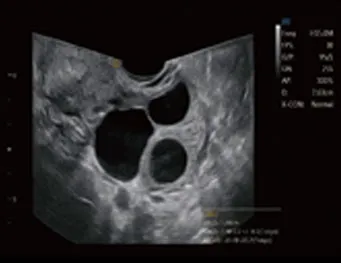

Sonda de TV de gran angular

● Ángulo extremadamente amplio de alrededor de 210°

● Proporcionar más información de diagnóstico

● Ahorre tiempo, mejore la eficiencia